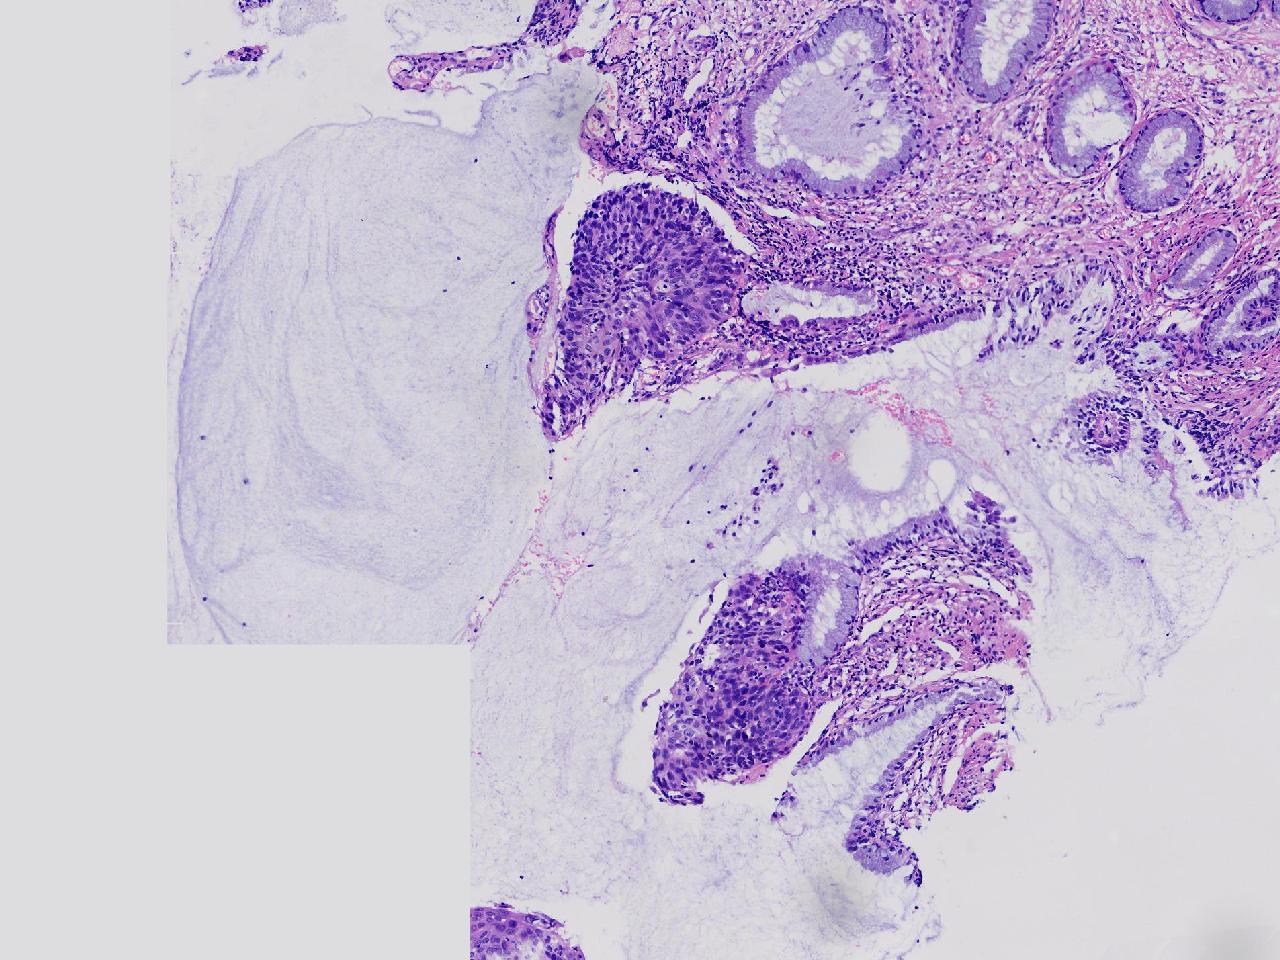

CIN2级?

女,46岁,宫颈活检。HPV16+

标本名称

宫颈活检

大体所见

宫颈多点活检。

CIN2...